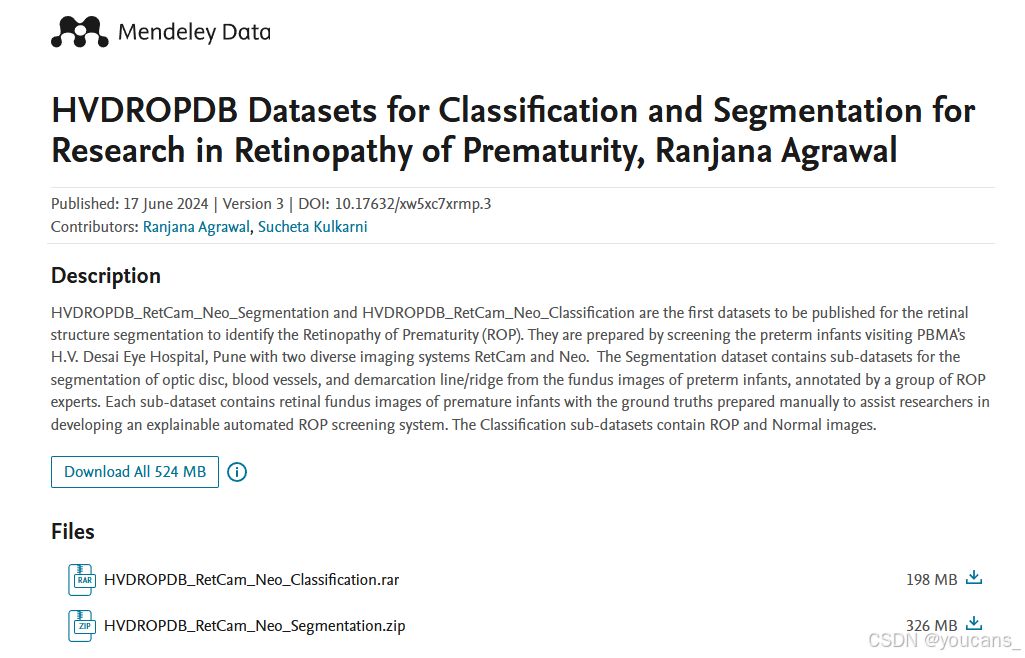

数据集的获取

本数据集保存在 Mendeley Data 数据平台,可以供研究者下载。

数据集下载: Mendeley Data/xw5xc7xrmp.3